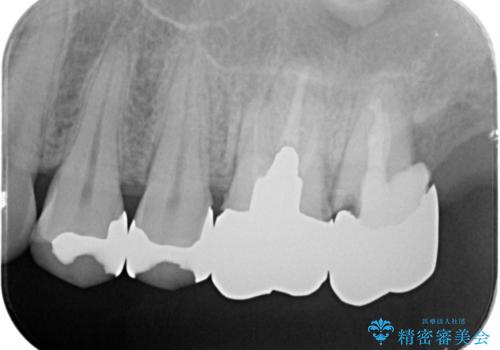

- 銀歯をやりかえたいが他院で抜歯と言われセカンドオピニオンで来院。適合の悪い被せ物が入っており、まずは古い材料、虫歯をとり保存可能か確かめる必要があり、拡大鏡下で全て取り除いたら歯質が歯茎の中まで虫歯がありました。このまま無理やり型取りをして被せ物を作っても不適合な被せ物が入る可能性が高いため歯茎を切り取る手術(ディスタルウェッジ)を行いました。そして再根管治療を行いゴールドの被せ物で治療を行いました。

- PGAクラウン・仮歯 13.2万円×2 精密根管治療(リトリートメント)・コア 16.5万円×2 ディスタルウェッジ 1万円費用は治療当時の料金となります